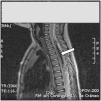

Lactante de 17 meses, con debilidad aguda de miembros inferiores (MMII) e irritabilidad, sin otra sintomatología acompañante ni antecedentes de traumatismo previo. Exploración: paraplejia flácida con nivel sensitivo D6, arreflexia en MMII, ausencia de reflejos cutáneos-abdominales y respuestas plantares indiferentes, siendo el resto de la exploración normal. Analítica básica incluyendo CK, normal. Ante la sospecha de enfermedad a nivel medular, como primera posibilidad una mielitis aguda, se realizó punción lumbar con LCR de características inflamatorias, iniciándose tratamiento con metilprednisolona intravenosa (30mg/kg/día). Horas más tarde presentó signos de disfunción autonómica (íleo paralítico, retención urinaria, priapismo). Ante la evolución rápidamente progresiva a síndrome medular completo grave, y para descartar completamente la posibilidad de comprensión extrínseca medular se realizó RM craneoespinal a las 36h del comienzo clínico, que mostró hematoma epidural espinal posterior desde D1 a L2, con edema medular desde C7 a D7 (figs. 1 y 2). Se practicó laminectomía y evacuación del hematoma, no encontrándose vasos patológicos intraoperatorios. La arteriografía espinal no mostró malformación vascular. La coagulopatía fue descartada. El paciente evolucionó hacia paraparesia espástica con vejiga neurógena.